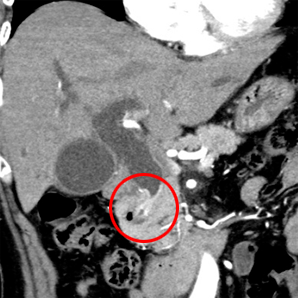

多目的デジタルX線TV装置を用いた胆道系検査・治療、肝腫瘍に対する血管造影検査・治療等を医師、看護師とともにチームで取り組んでいます。

造影検査等の最新技術を用いた精密検査も積極的に行っています。